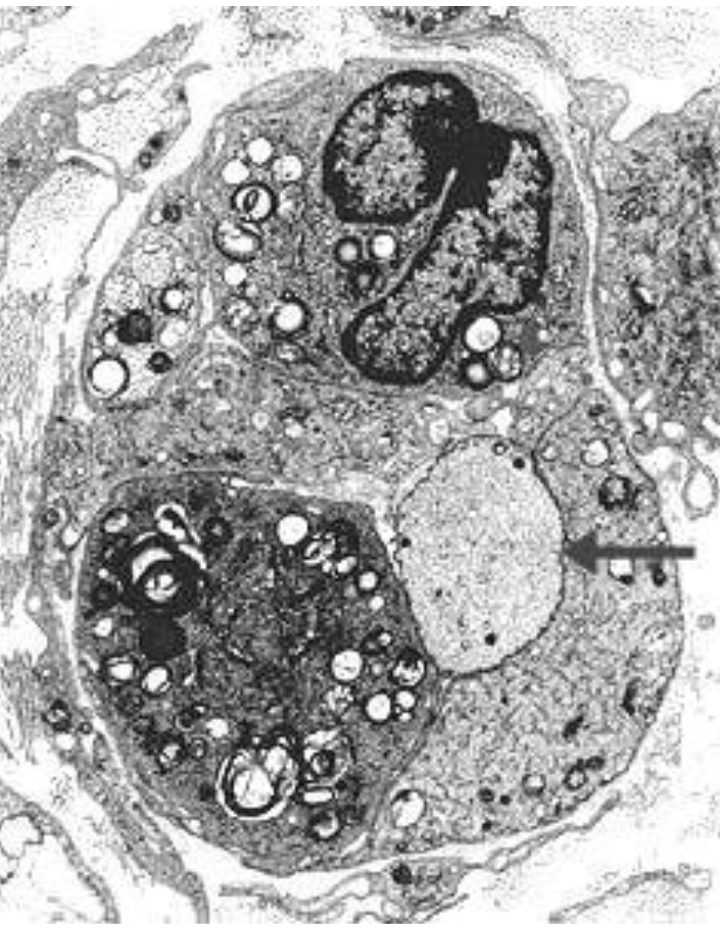

Demyelinated axon. Note good preservation of the axoplasm. Myelin debris from

myelin breakdown is present within cytoplasmic processes of macrophages